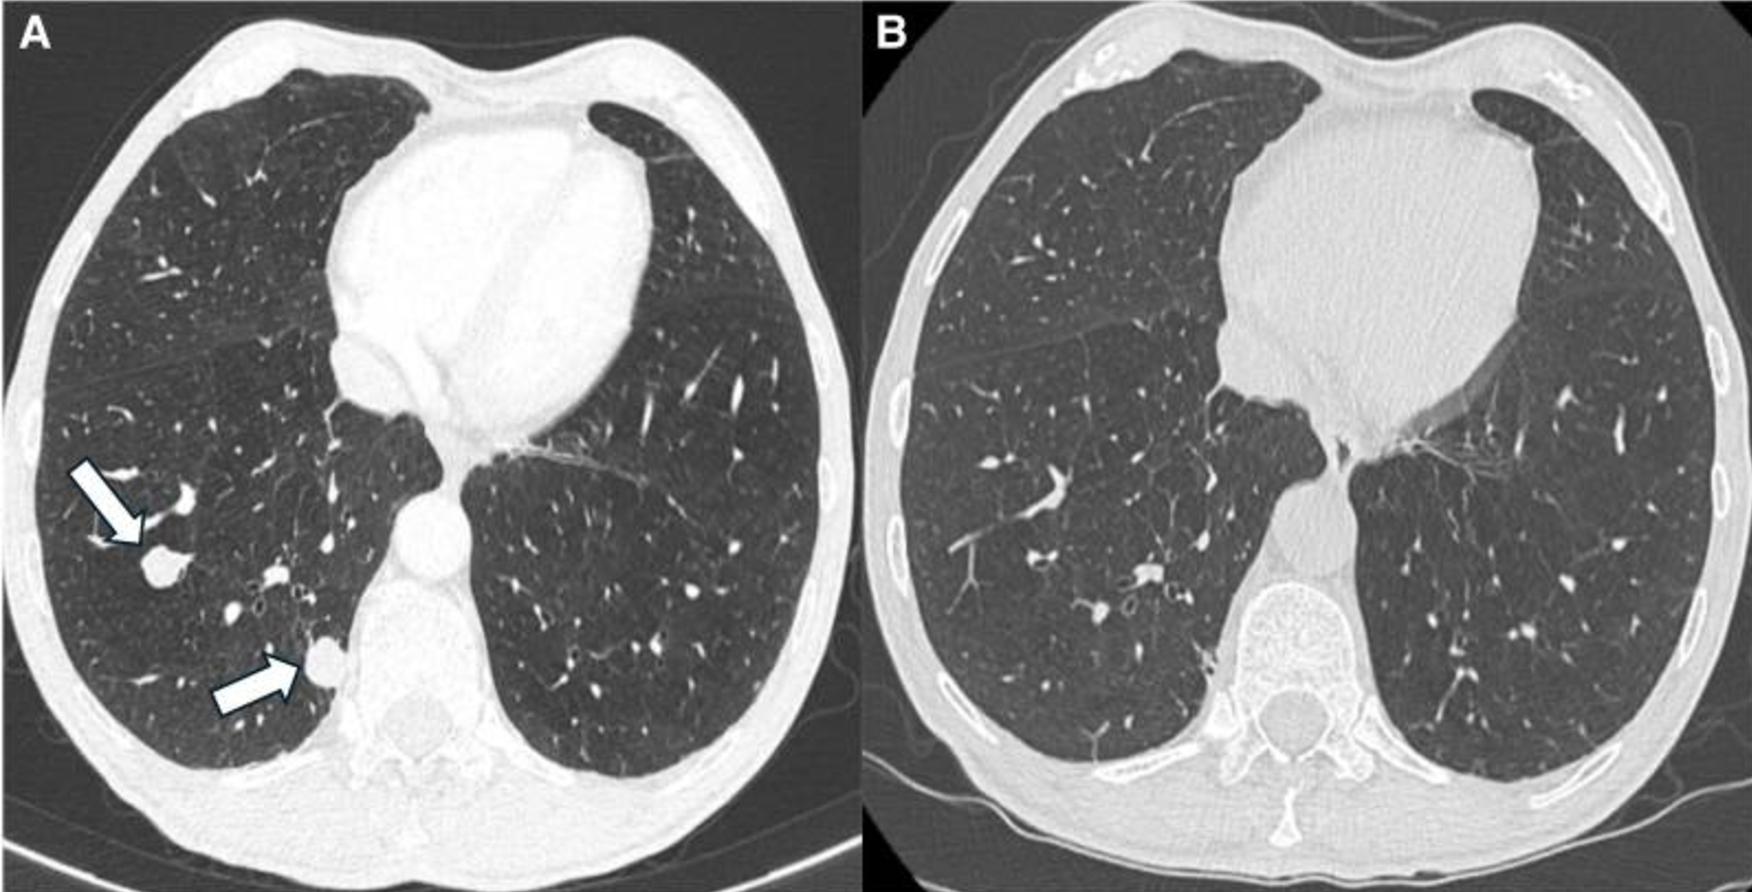

MRI证实存在增大的不均匀左肾上腺肿块,并伴有强烈的对比增强(图3A-3C)。此外,肝脏中描述了2个新的可疑病变,其中1个在第VIII段为2cm,另一个在第VI段为7.7mm,倾向于转移性疾病(图3A-3C)。胸部CT还显示了多个继发性双侧肺部病变(图4A)。18FDG-PET显示,肾上腺病变(18SUVmax)、肝和肺病变(10-12SUVmax)和左肾上腺静脉(12SUVmix)的摄取增加,与血管血栓一致(图2)。

图4 患者治疗前后肺部CT。初始表现(A)的轴位CT图像显示右下叶有2个边界清晰的肺结节(箭头),与转移一致。治疗6个月后,相同水平(B)的相应CT图像显示转移结节完全消退

两种治疗后3个月的成像显示,所有病变都有部分反应,6个月时,根据RECIST 1.1标准,肾上腺和肝脏病变有进一步的部分反应(图3D-3F),肺转移完全消失(图4B)。患者在ACC诊断后8个月仍然活着,仅继续接受米托坦治疗。